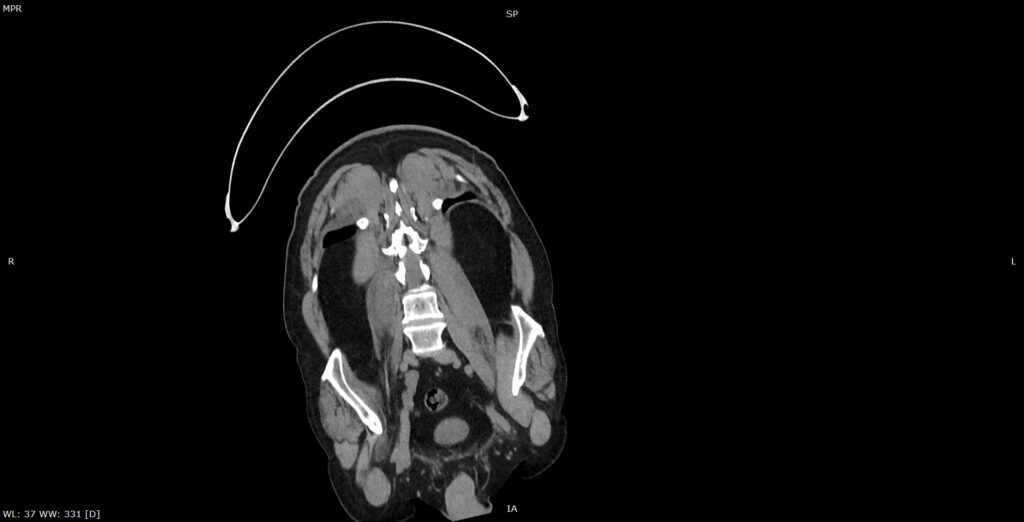

Figura 3: reconstrucție oblic coronală din achiziție CT fără contrast posttraumatic imediat

Discuţie caz nr 134: Pe imaginile achiziționate fără substanță de contrast se remarcă creștere marcată de volum a muschiului ilio-psoas drept în două treimi distale cu evidențierea unei plaje întinse cu densități sangvine ce sugerează prezența unui hematom posttraumatic; nu se evidențiază traiecte de fractură. Achiziția de control după 22 de luni evidențiază reducerea grosimii corpului muscular ilio-psoas drept cu încărcare grăsoasă care, pe alocuri, afectează aproape complet corpul muscular.